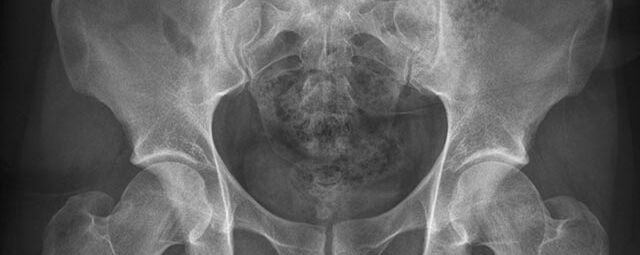

Konventionelles Röntgen

Der Begriff Röntgen, oder auch Röntgendiagnostik bezeichnet ein Verfahren in der Radiologie, bei dem von einer Röntgenröhre elektromagnetische Wellen (Röntgenstrahlen) durch die zu untersuchende Körperregion des Patienten gesendet werden. Je nach Dichte der Gewebeart des Körpers (z.B. Knochen oder Lunge) werden die Röntgenstrahlen im Körper unterschiedlich stark abgeschwächt. Ein digitaler Detektor empfängt dann die Röntgenstrahlen, die in abgeschwächter Form den Körper wieder verlassen haben. Daraus wird das Röntgenbild erzeugt.

Die Röntgenuntersuchung ist weiterhin eine unverzichtbare Basisdiagnostik. Viele Fragen können in der medizinischen Diagnostik mit einer konventionellen Röntgenaufnahme geklärt werden.